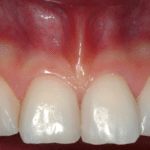

Il concetto di malattia parodontale è basato essenzialmente su due componenti, da una parte un complesso microbico altamente eterogeneo, assai attivo, stabilmente aderente alle superfici dentarie denominato placca batterica e, dall’altra parte, un parodonto (tessuti che circondano il dente) che viene “infiammato” da questi batteri e dai loro prodotti con una sintomatologia clinica data da cambiamento di colore (da rosa a rosso scuro), edema (ingrossamento del “complesso gengivale”) e sanguinamento sia spontaneo (nel cuscino al mattino) che provocato (spazzolamento).